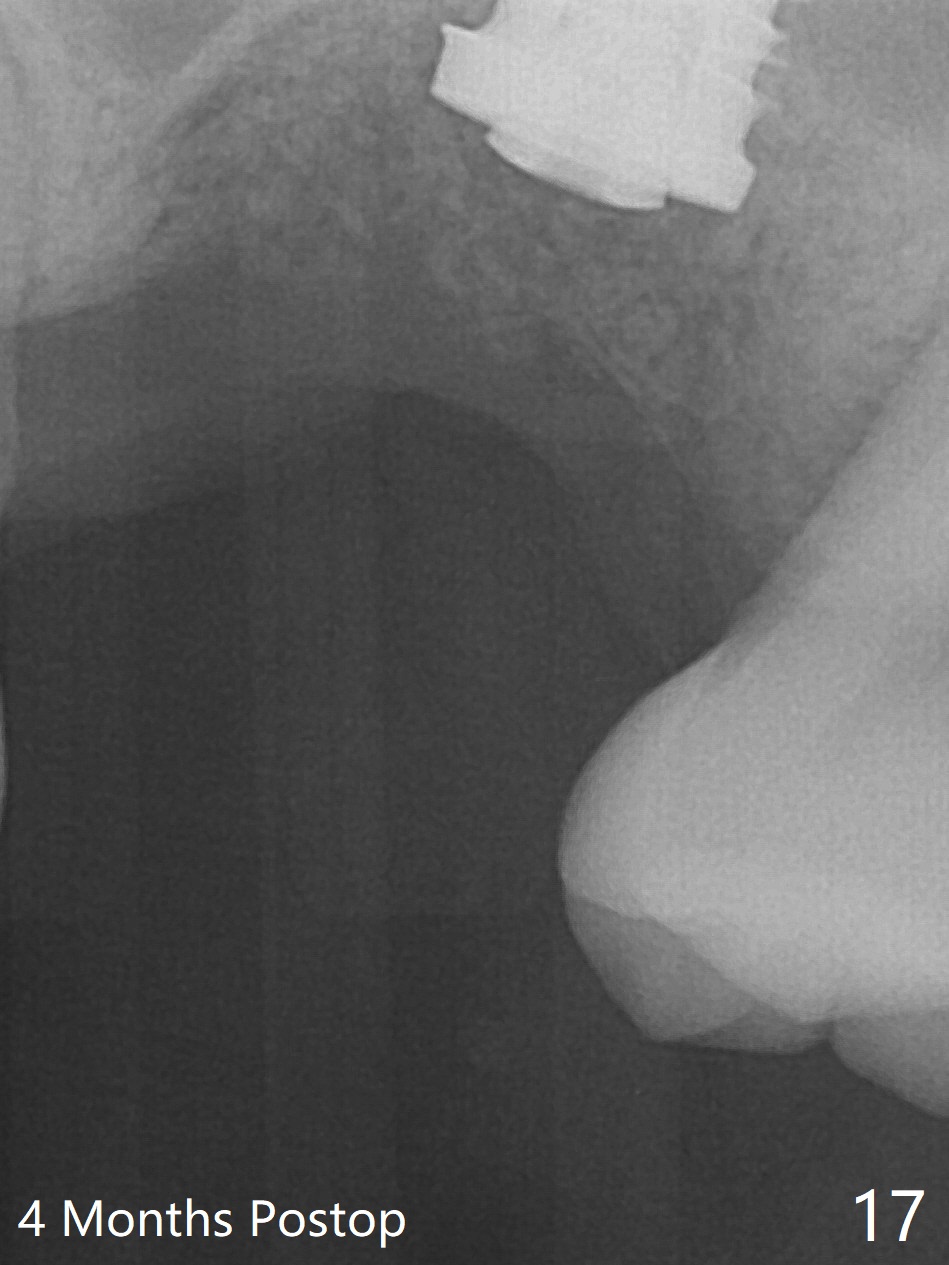

Poor visibility for immediate implant in the molar region is another contributing factor for the dislodgement.  The patient returns for follow up 15 days (Fig.15) and 1 month (Fig.16) postop.  Bone graft seems to be stable around the implant.  The socket heals 4 months postop (Fig.20).  The implant seems to have been osteointegrated (Fig.17,18).  It will be backed up for ~ 3 mm to improve implant/crown ratio (Fig.19, as compared to Fig.14).  If it cannot be done, take impression immediately and make a subgingival provisional before suturing.

In fact, there is no coronal bone for the implant to be backed up.  Therefore, impression is taken after uncover and insertion of a 5.5x5.7(4) mm abutment.